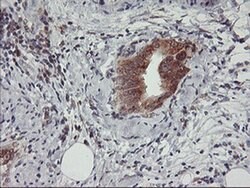

USP10 Mouse anti-Human, Clone: OTI1A10, liquid, TrueMAB™

Ubiquitin is a highly conserved protein that is covalently linked to other proteins to regulate their function and degradation. This gene encodes a member of the ubiquitin-specific protease family of cysteine proteases. The enzyme specifically cleaves ubiquitin from ubiquitin-conjugated protein substrates. The protein is found in the nucleus and cytoplasm. It functions as a co-factor of the DNA-bound androgen receptor complex, and is inhibited by a protein in the Ras-GTPase pathway. The human genome contains several pseudogenes similar to this gene.Specifications

| Flow Cytometry, Immunohistochemistry (Paraffin), Western Blot | |